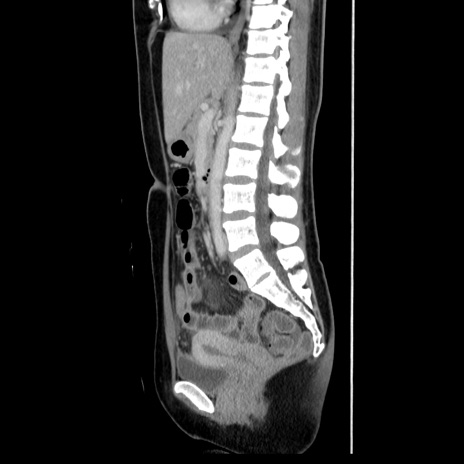

症例39(矢状断像)

【症例】40歳代女性

【主訴】上下腹部痛

【現病歴】2日目から下腹部痛あり。夜間は痛みで眠れなかった。昨日より上腹部痛と下痢が出現。臥位で痛みは軽快したため、休んでいた。本日になって臥位でも立位でも痛みが強くなってきたため救急要請。

【既往歴】子宮内膜症

【身体所見】部:平坦・軟、左上下腹部に圧痛あり、反跳痛あり。

【データ】WBC 21800、CRP 26.78

CT